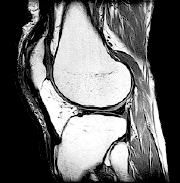

MRI. This detailed imaging test can show bone, cartilage, ligament, or muscle problems, without using X-rays.

| Imaging tests such as an MRI scan may help your healthcare provider find the cause of your knee problem. |